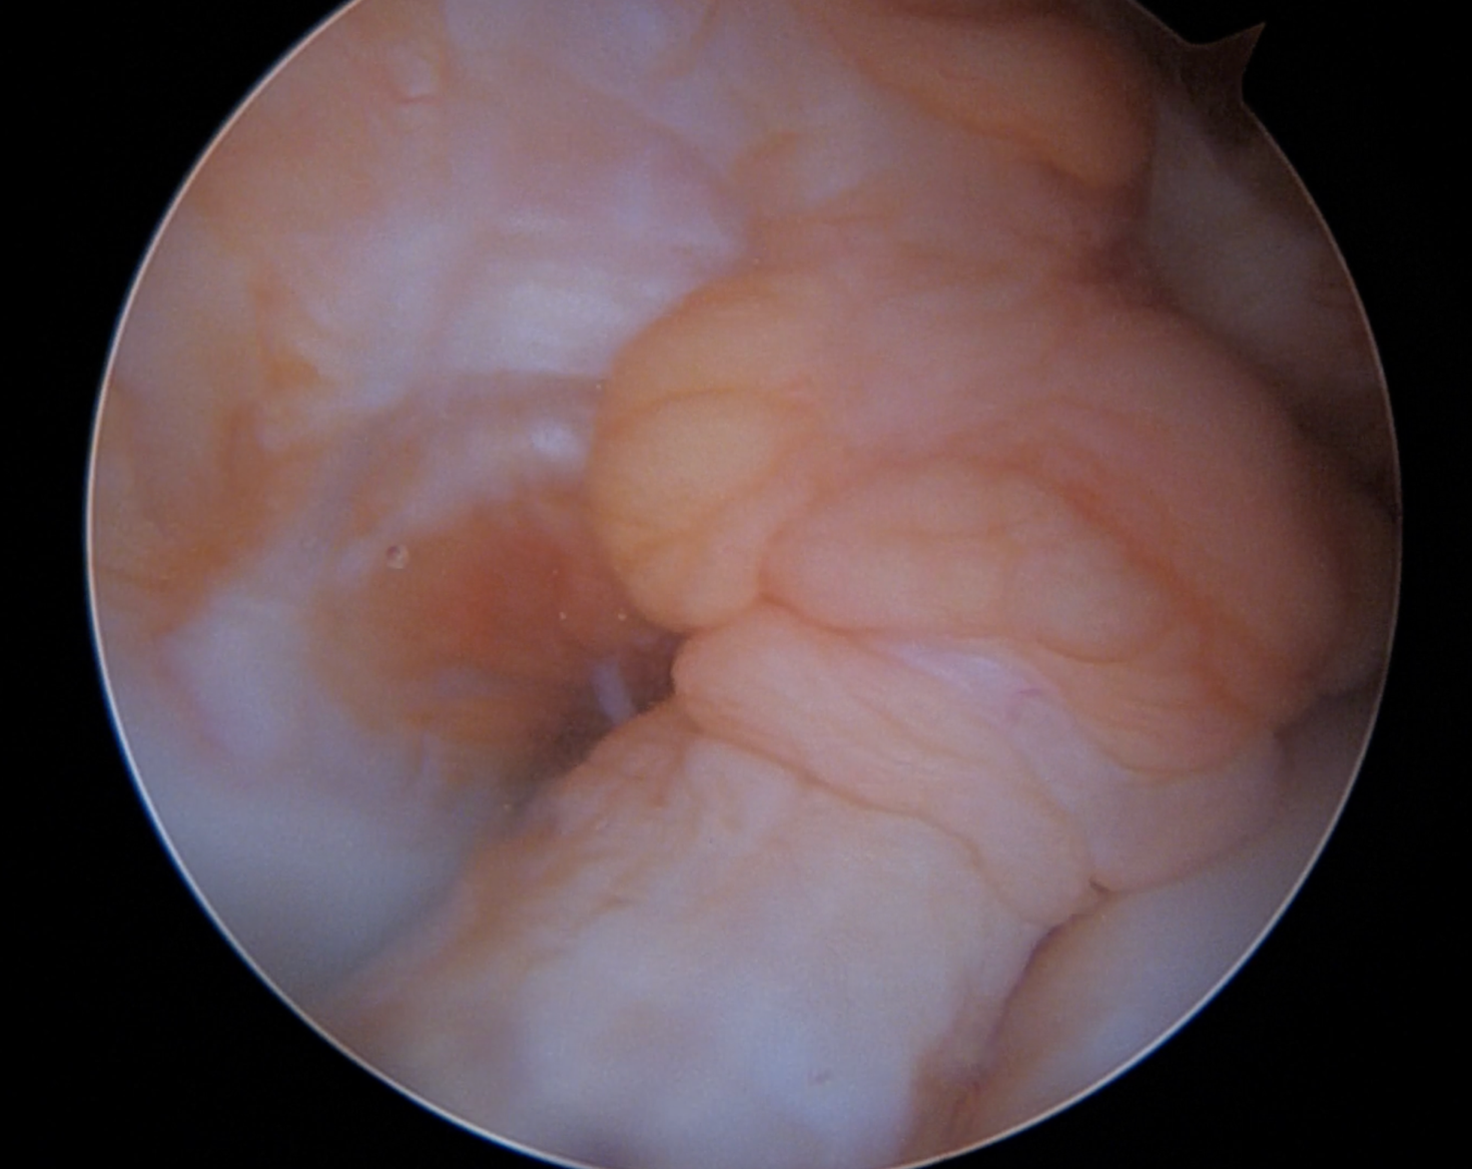

La possibilità di riparare – anziché ricostruire – il LCA si basa sui presupposti biologici secondo cui il tessuto legamentoso nei pazienti pediatrici presenta una maggiore capacità rigenerativa, potenzialmente superiore rispetto all’adulto (1). Inoltre, alcune lesioni del LCA, in particolare quelle prossimali, possono presentare una qualità del tessuto legamentoso tale da consentirne più agevolmente la reinserzione anatomica. Infatti, già nel 1991, Sherman et al. (2) identificarono una classificazione delle lesioni del LCA basata sulla localizzazione, evidenziando che le lesioni di tipo 1 – avulsione del legamento a livello dell’inserzione femorale – e tipo 2 – lesione del legamento entro il 20% della sua lunghezza a livello femorale – presentavano una prognosi migliore rispetto alle lesioni di tipo 3, 4 e 5 in caso di riparazione. Studi successivi hanno confermato che il terzo prossimale del LCA possiede un potenziale di guarigione intrinseco simile a quello del legamento collaterale mediale (3).

Negli ultimi anni, lo sviluppo di tecniche artroscopiche mini-invasive ha reso la riparazione del LCA tecnicamente più sicura e riproducibile. Le metodiche più utilizzate prevedono l’utilizzo di suture ad asola, spesso associate a fissazione con ancorette riassorbibili o dispositivi corticali sospensivi. La ricerca continua a portare innovazioni: negli Stati Uniti, l’attenzione si è focalizzata sull’uso di suture tape come supporto biomeccanico, mentre in Europa è stato introdotto il sistema di stabilizzazione intralegamentosa dinamica (DIS), che prevede l’utilizzo di un impianto a molla ancorato alla tibia che applica una forza di detensionamento al LCA durante il processo di guarigione.